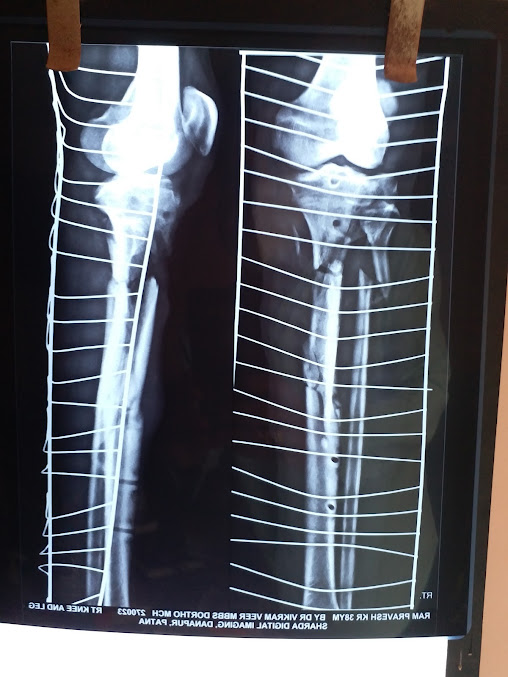

Hospital Gallery

The Veer Hospital is committed to providing affordable, quality health care to patients by incorporating improvement in its day-to-day schedule.